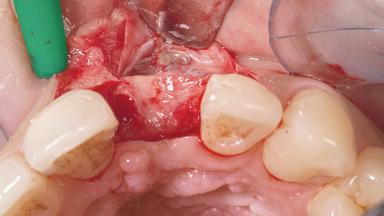

Late Placement of an Implant in a Maxillary Left Central Incisor Site

A 30-year-old female patient had lost tooth 21 and was referred to our clinic for consultation and treatment. Due to advanced apical infection, tooth 21 had been extracted two months earlier at another clinic and an acrylic-resin tooth had been bonded to the adjacent teeth. The patient desired implant treatment to avoid any damage to the adjacent natural teeth. While the patient had no history of any systemic disorder, she was a heavy smoker and exhibited medium to advanced periodontitis in the entire jaw. After the initial treatment to achieve a pocket probing depth of less than 4 mm and no bleeding on probing, a decrease in the height of the papillae mesial and distal to the extraction site and overall gingival recession were observed.

Bone Augmentation Horizontal|Staged

Augmentation Materials Autogenous chips|Membrane

Soft Tissue Grafting Simultaneous

Bone Volume Horizontally and vertically sufficient Horizontally deficient Deficient vertically or deficient vertically AND horizontally

Bone Volume Deficient horizontally, requiring prior grafting